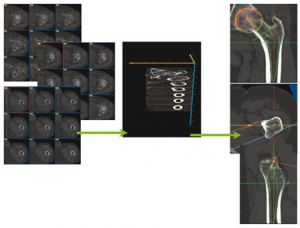

Ce logiciel de planification permet à l’utilisateur de simuler la mise en place des composants prothétiques après avoir défini les principaux repères anatomiques de la hanche à opérer. Cette mise en place virtuelle des composants prothétiques permet de les visualiser dans les 3 plans de l’espace et d’apprécier leur volume et leur retentissement sur les segments osseux (allongement, médialisation, latéralisation, torsion…).

Fig 1 : Simulation et planification 3d a partir du scanner préopératoire.

La simulation prothétique permet le choix du type et de la taille des composants qui semble la mieux adaptée à la hanche à prothèser. Elle visualise leur placement dans les plans de référence.